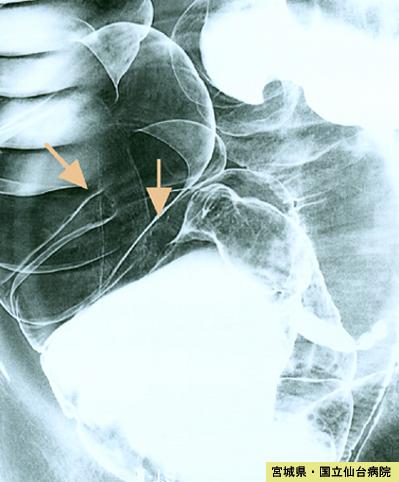

Múltiples Metástasis de Cáncer del Intestino Delgado y Grueso que mostraron forma similar a IIa+IIc (Caso presentado por Dr. Yokota del Hospital Nacional de Sendai, prefectura de Miyagui)

[Image-ID:3946]

Tumor de tipo Metastásico/

parte(separada por órganos)

colon/ascendente

método de exámen

Rayos X

diámetro mayor del tumor

10 - 14